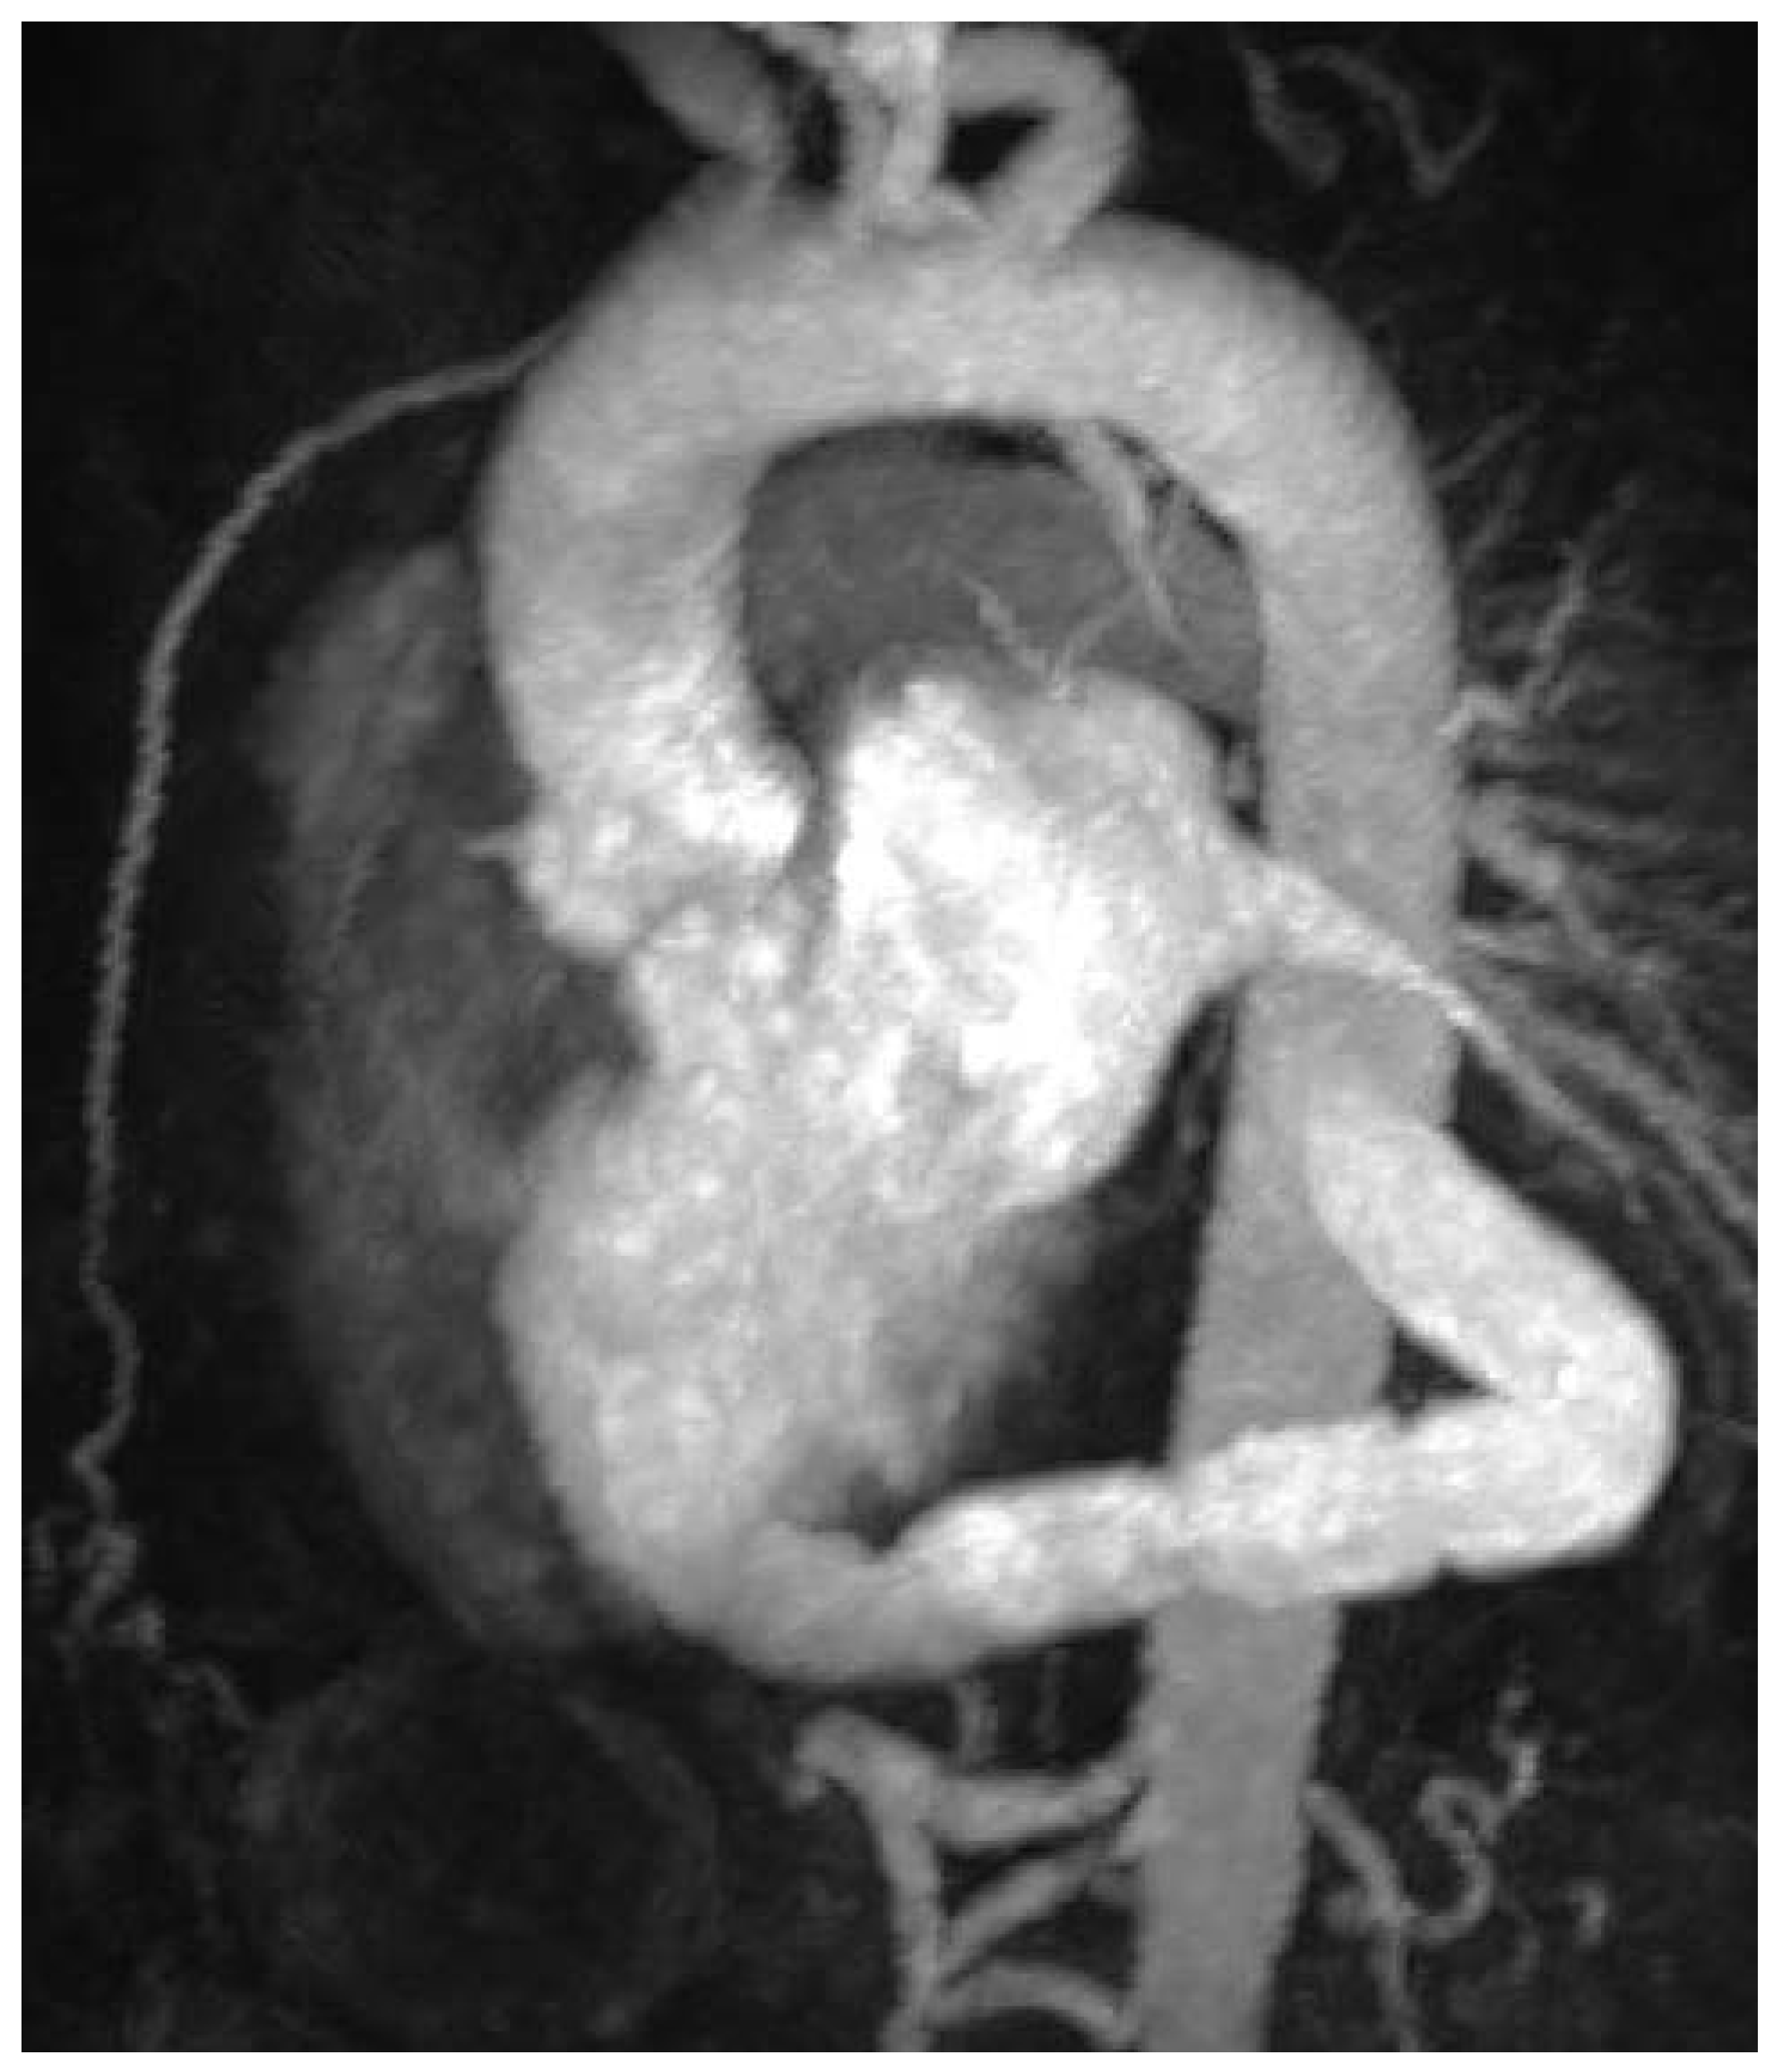

Figure 4. Postoperative MRI showing correct position of the AVB.

A MRI scan of the heart was performed on day fourteen after surgery. Flow measurement demonstrated 55% of cardiac output passed via conduit. Cardiac output of 2.1 l/min was measured in the ascending aorta and of 2.6 l/min in the descending aorta, with a total of 4.7 l/min. Minimal flow was shown in the descending aorta distal to the subclavian artery and proximal to the conduit. Bioprosthetic regurgitation was excluded in the MRI.